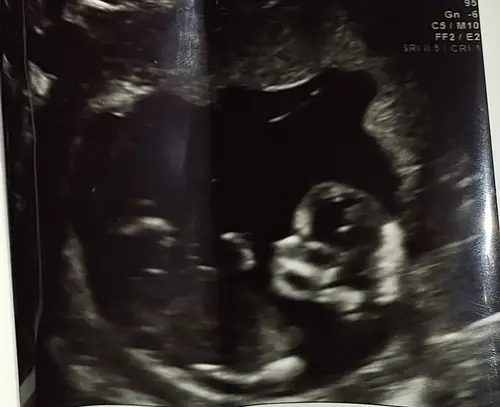

Dit is wat we mee hebben gekregen, ik kan er iniedergeval weinig van maken

Dat is wel slecht zeg. Vrienden van ons hadden ook zo’n echo, alleen zijkant bekeken “het is een jongetje” en bij 20 weken bleek het toch een meisje. Ontzettend slordig